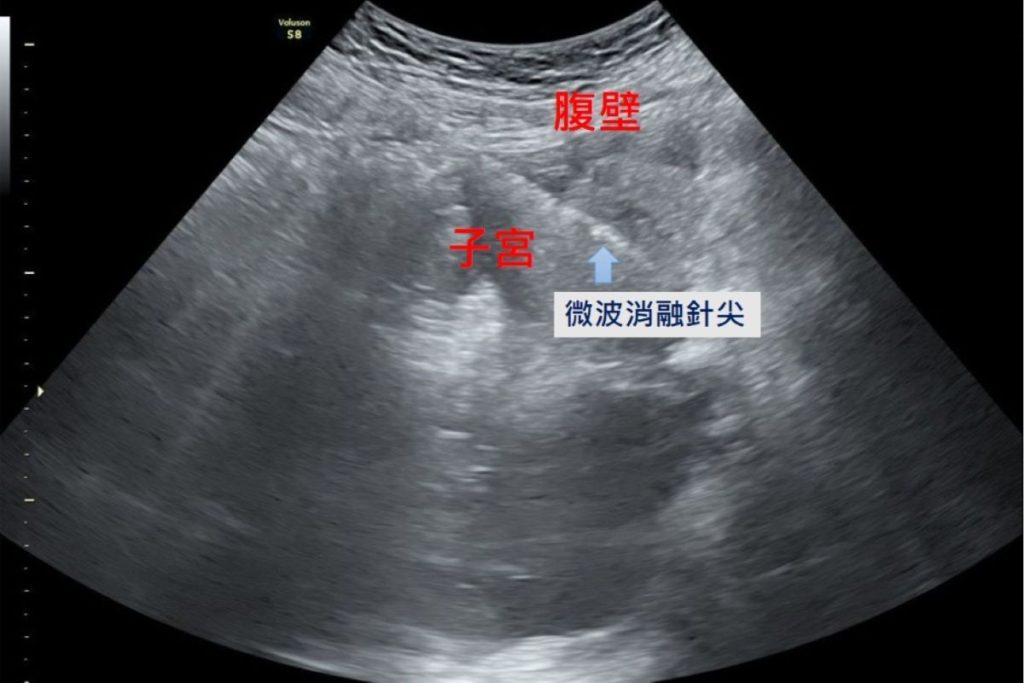

隨著醫療科技的進步,微波消融成為近年來的治療新選擇。醫師在腹腔鏡及婦科超音波的導引下,將消融針精準進入病灶,釋放高能量微波破壞異常內膜腺體組織,使其失去活性而逐漸縮小壞死,達到止痛與減少經血的治療目的。

陳國瑚表示,微波消融治療的範圍可透過影像導引精準掌握,不容易傷害周邊組織;也因為術中保護子宮內膜,病人術後不影響懷孕。此外,微波消融治療術後疼痛感低、併發症風險也較小。根據臨床追蹤,近9成的病人預後狀況良好,能恢復正常月經週期,經痛大為改善,提升生活品質。